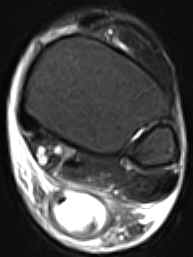

• Partial Rupture:

• There is  partial continuity of a portion of the tendon fibres on at least one sagittal section. There is no tendinous gap.

• The tendon may be thickened and usually exhibits focal areas of intermediate signal intensity on the T1W images and increased signal intensity on the T2W images due to edema and/or hemorrhage.

• It may be difficult to differentiate between tendinitis and partial tears as the two often coexist. In uncomplicated chronic tendinitis there is focal or diffuse thickening of the tendon without increased intrasubstance signal intensity.